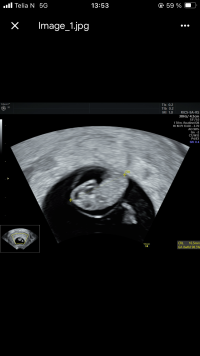

Hei, Jeg vil bare si ifra om at personnummeret ditt med på bildetBle satt fram en dag, så 8+1 i dag veldig godt å se og høre at alt sto bra til

fine hjerteslag på 162